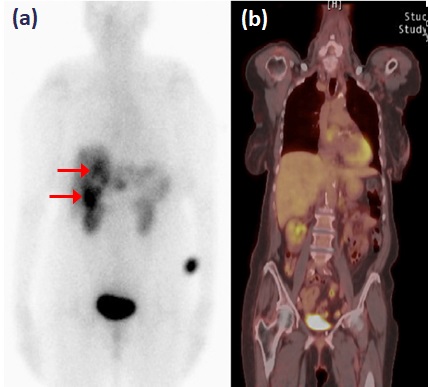

FDG-PET-CT é um exame de baixa sensibilidade na avaliação do TNE bem diferenciado (figura 2), ao passo que a taxa de detecção é alta em pacientes com Ki-67 superior a 15%. Em um estudo prospectivo, a sobrevida mediana de pacientes com FDG-PET-CT negativo e positivo foi de 119,5 meses e 15 meses, respectivamente (P<0,001) (BAHRI, 2014). Um FDG-PET-CT positivo, assim, sugere menor diferenciação tumoral e exige que se considere a necessidade de intervenções terapêuticas mais rigorosas.

Figura 2: Exames funcionais de tumor neuroendócrino bem diferenciado metastático. Captação em fígado (setas) ao Octreoscan (a), mas não ao FDG-PET-CT (b). Adaptado de Leung et al, 2013.